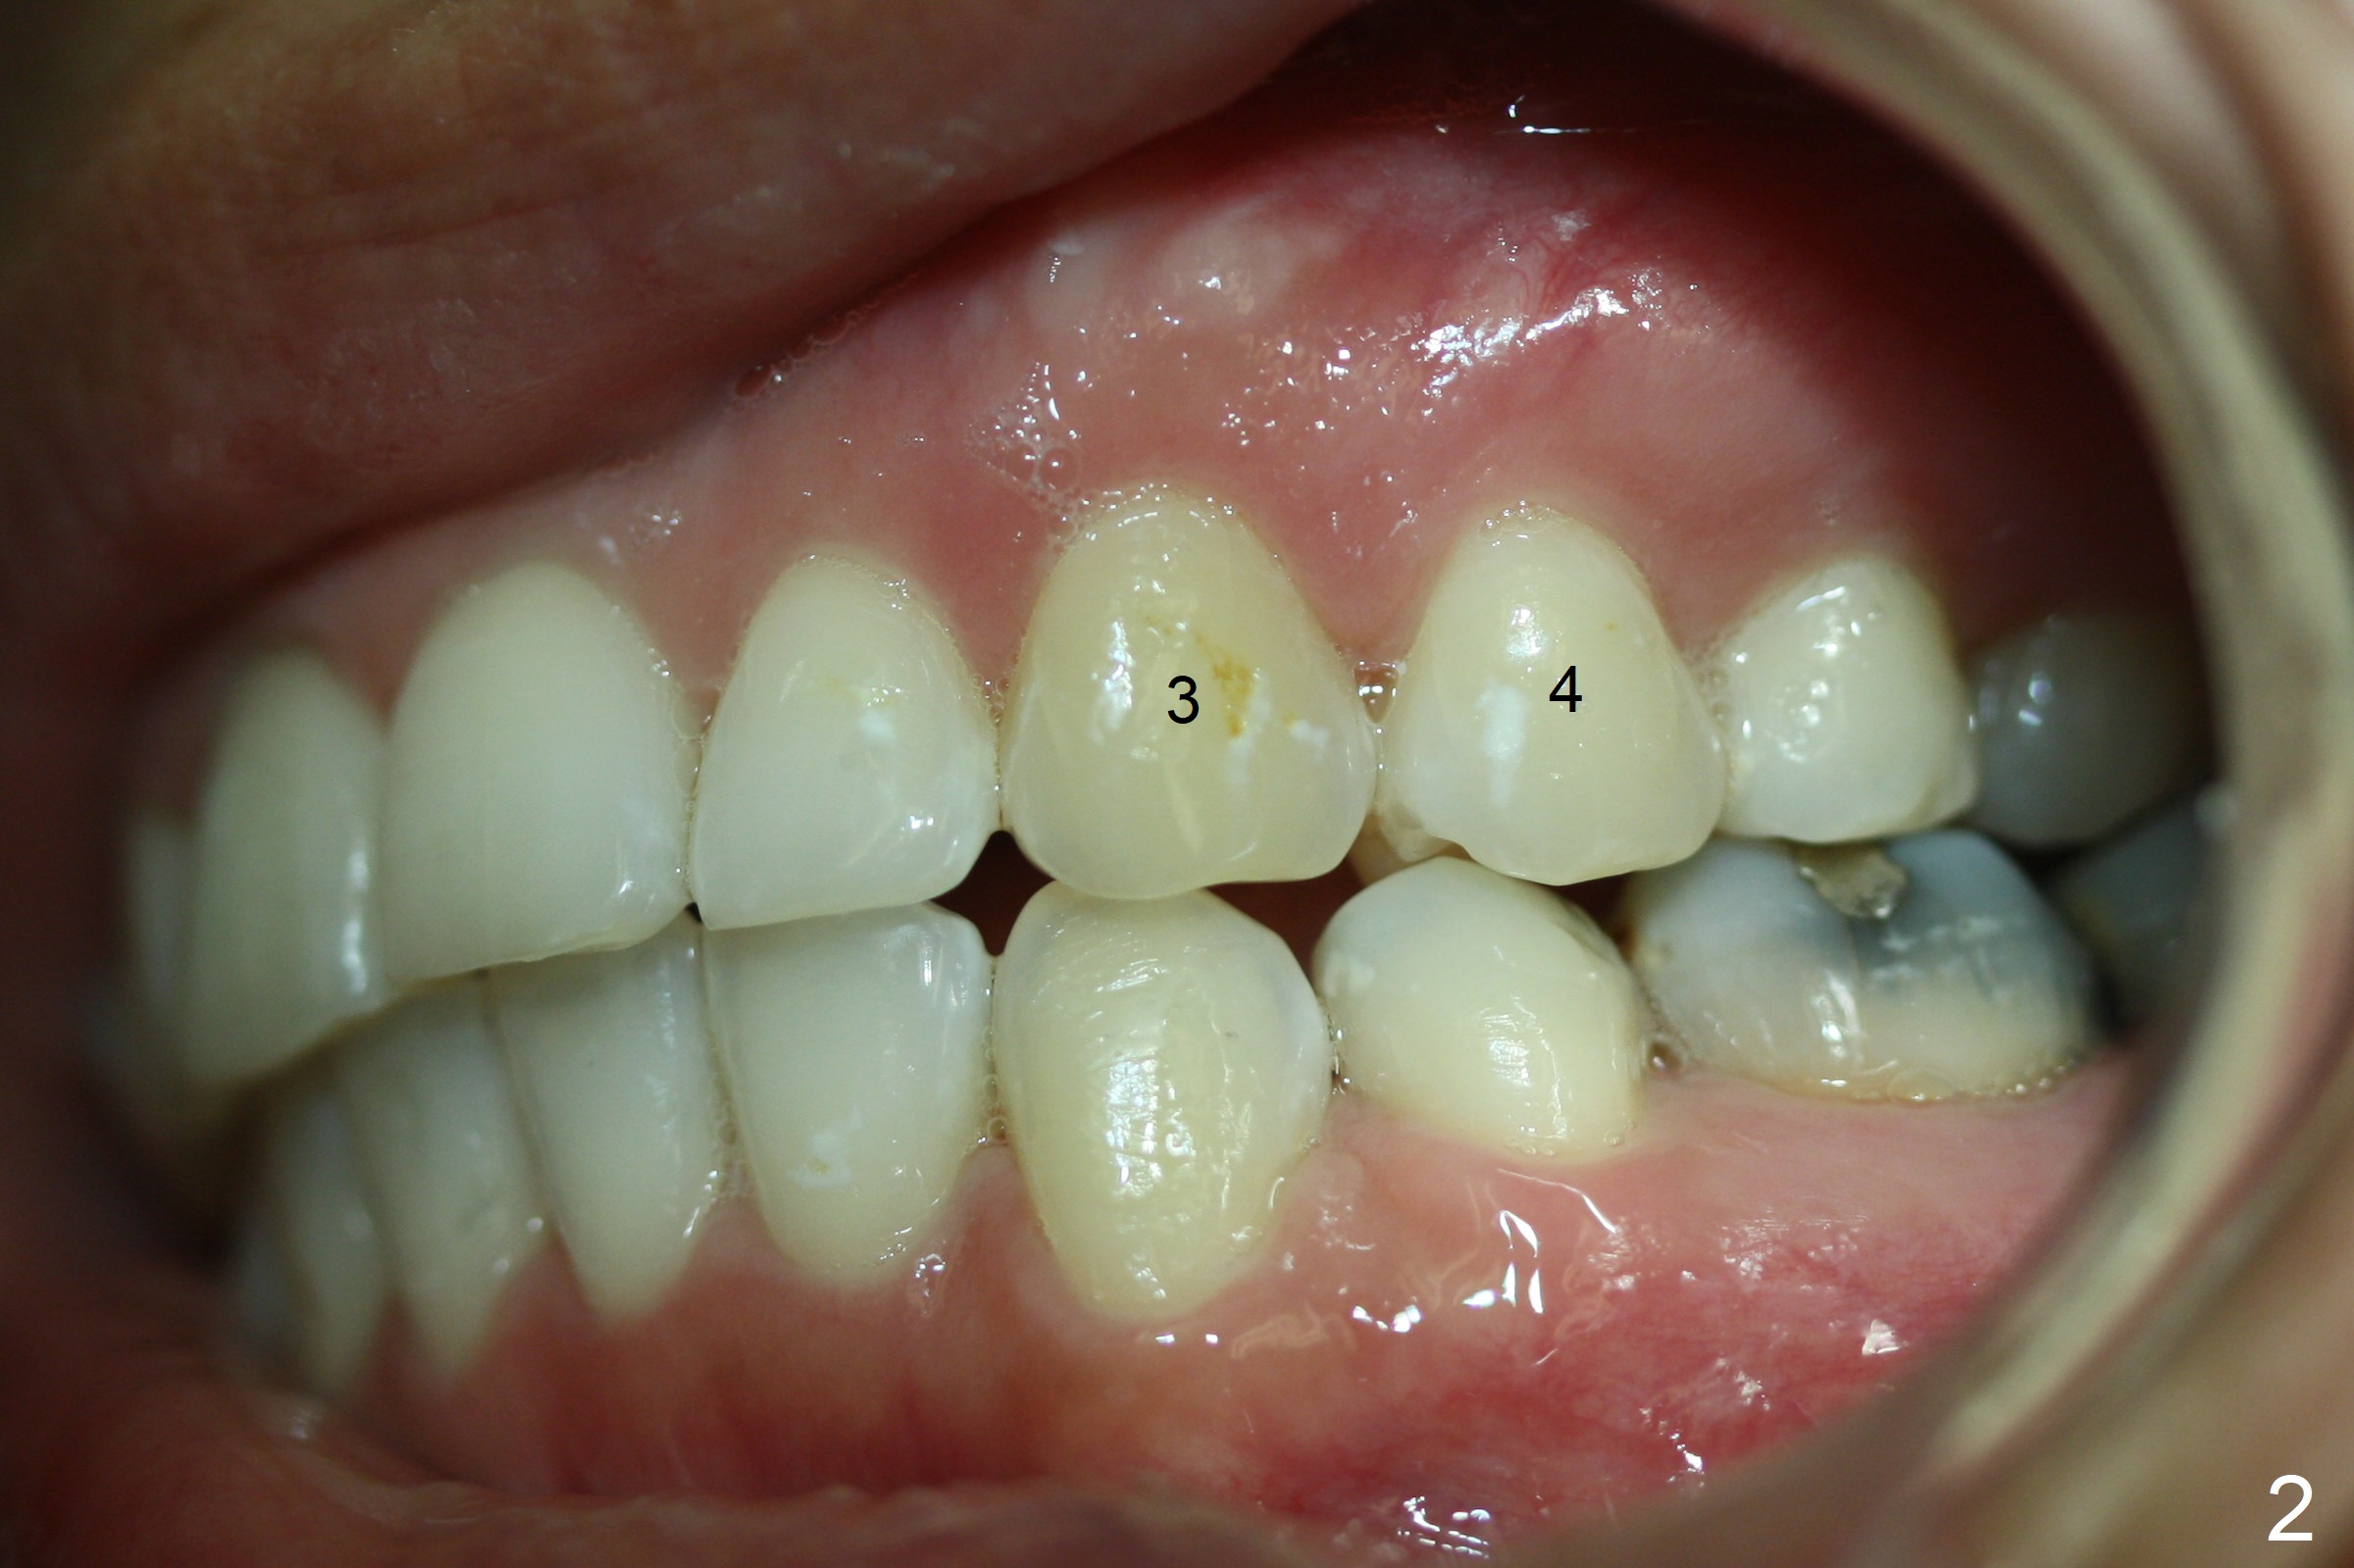

Discoloration of Upper Canines and

1st Bicuspids

Five months post debanding, the upper right canine becomes transiently symptomatic (tender to touch). Although both the right (Fig.1) and left (Fig.2) canines (3) and 1st bicuspids (4) discolor, the right ones are necrotic (pulpal test). It appears that these two teeth have periapical radiolucency (Fig.3,4), while the lateral incisor has shortened root (2). The longest tooth (upper canine) appears to be the most vulnerable to trauma associated with orthodontic movement.